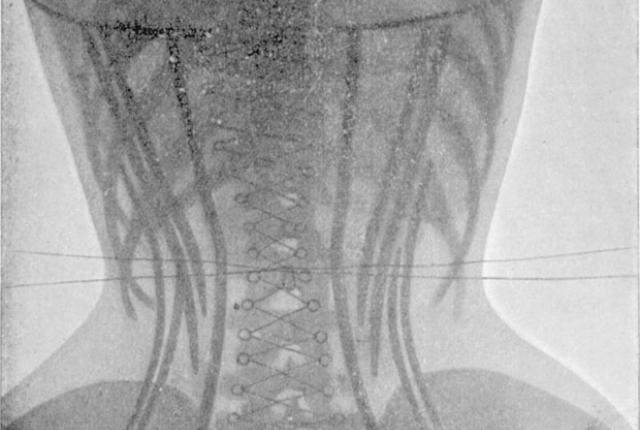

1. Корсеты

Знаете, что кажется мужчинам особенно скучным? Пышущий здоровьем женский организм, вот что! Зачем, вы думаете, в 19 веке сильный пол с таким усердием охотился на китов? Чтобы женщины могли утягивать свои тела корсетами из китового уса и калечить внутренние органы, конечно.